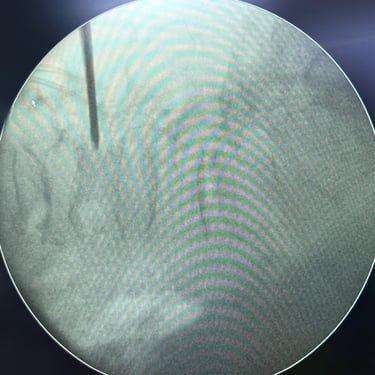

Fractura Lumbar Osteoporótica / Vertebroplastía y Bloqueo Lumbar Selectivo

La fractura lumbar osteoporótica y la artrosis lumbar son causas frecuentes de dolor crónico y limitación funcional en el adulto mayor. La osteoporosis debilita las vértebras, favoreciendo fracturas incluso ante esfuerzos mínimos, mientras que la artrosis genera desgaste articular e inflamación. La vertebroplastía percutánea permite estabilizar las vértebras fracturadas mediante la inyección de cemento óseo, proporcionando alivio rápido y mejorando la movilidad. En casos de dolor persistente por artrosis, el bloqueo lumbar selectivo ayuda a reducir la inflamación y el dolor. Ambas técnicas son procedimientos mínimamente invasivos que mejoran la calidad de vida y facilitan la recuperación funcional.